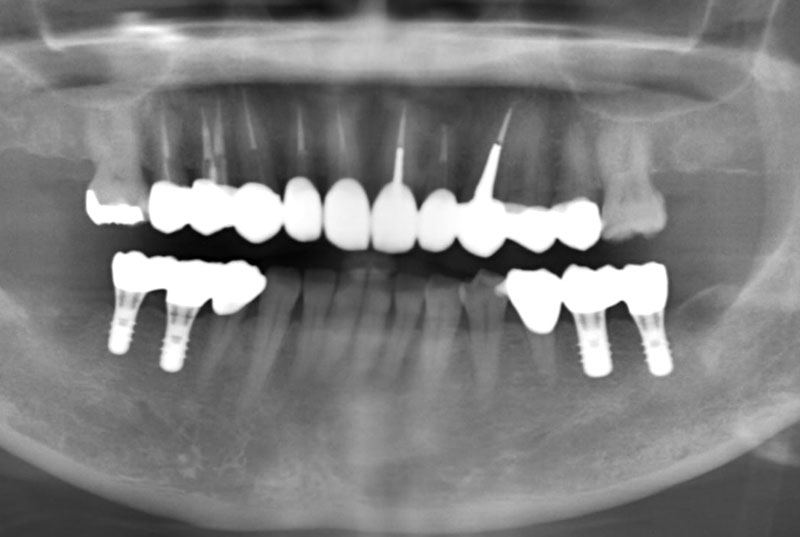

歯歯やあごの骨の状態を正確に把握するため、当院ではCTなどの検査機器を使用しています。

CT検査では、骨の密度(硬さ)をはじめ、神経までの距離や骨の厚み、骨質の状態まで詳細に確認することができます。

これにより、安全性を重視したインプラント治療を行うための的確な検査と診断が可能になります。 -